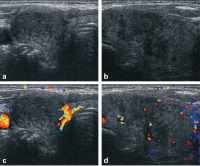

Abbildung 4: Dopplersonografisch keine gesteigerte Perfusion.

Abbildung 6a-d: Anderer Patient, anderes Ultraschallgerät: Auch hier sowohl im Querschnitt (6a) und im Längsschnitt (6b) des rechten Lappens konfluierende echoarme Areale inmitten von regelrechtem Schilddrüsenparenchym. 6c, d: Dopplersonografisch keine gesteigerte Durchblutung (c-Querschnitt und d-Längschnitt).